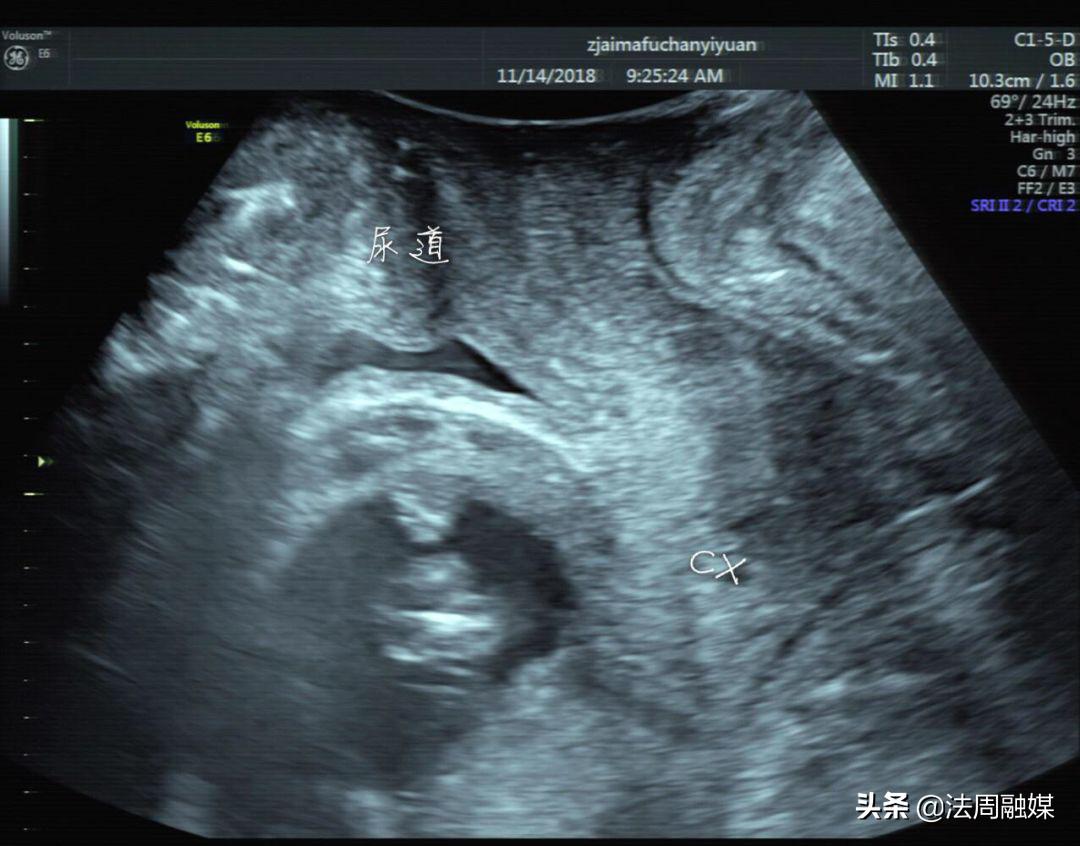

尿潴留缓解,子宫位置已转前位,宫颈远离尿道